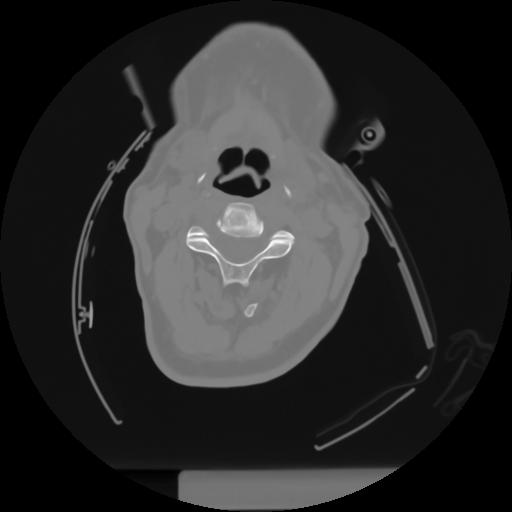

10 P.BLANDAS,,Axial,2.0,P.BLANDAS,,